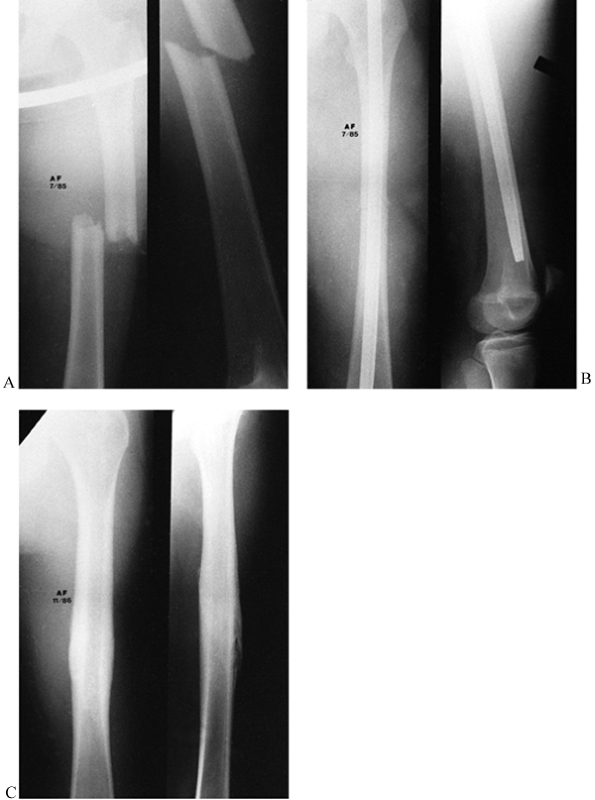

![]() |

Figure 20.2. A: The classic indication for medullary nailing of a short, oblique, mid-isthmus fracture. B: A standard medullary nail is placed. C:

After removal 16 months later, there is a smooth, well-remodeled callus, and the general shape of the bone is quite normal, with no significant varus or valgus and some maintenance of an anterior bow. Ideally, a medullary nail should restore this normal anterior bow and result in a normal position of the knee. Because the pattern and location of the fracture allowed secure fixation with a standard medullary nail, no interlocking was performed, although I now lock nearly all nails. The nail was intentionally left slightly short in this fracture because an open epiphysis was present distally, even though this patient was very close to the end of growth. Additionally, cancellous bone near the knee is quite dense in young patients, making it difficult to drive the nail farther. |